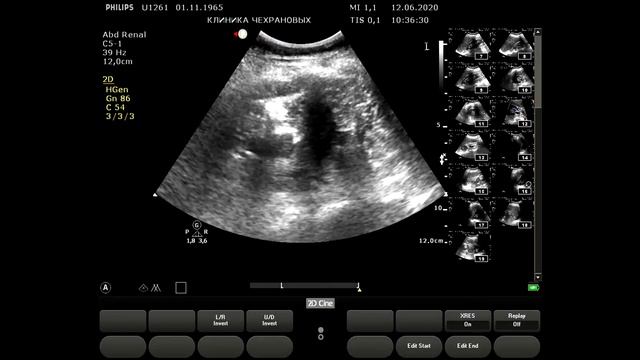

УЗИ БЦА - норма визуализация идеальная. Тот случай когда на обследование БЦА уходит 4 минуты без описания а описание минут 5-6. Для такой категории пациентов 20 минут на вполне достаточно. Но такой пациент скорее исключение из правил. УЗИ сердца - норма. На 12-й минуте - определение индексированного объема левого предсердия определение диастолической функции левого желудочка по тканевому допплеру.,